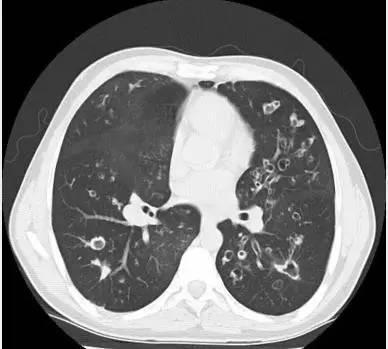

他的临床表现为反复发作的呼吸系统感染伴排痰性咳嗽,喘鸣音及呼吸困难。CT表现为支气管扩张症,通常累及所有的肺叶,但是倾向于肺上叶最严重。